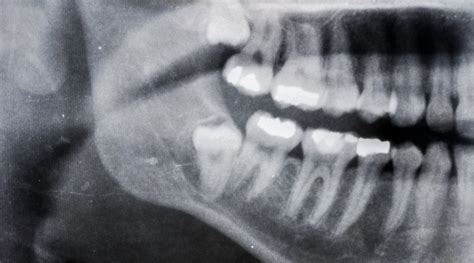

El diente de leche hace las funciones de guía del permanente, marcando el camino por donde debe salir. Si el de leche se cae antes de tiempo, el definitivo pierde la guía para hacer erupción. En caso de que esto ocurra, es posible encontrar la ubicación del diente mediante una radiografía y entonces hacer el tratamiento adecuado. Otra causa puede ser un traumatismo en los dientes de leche, que terminan empujando el definitivo hacia el hueso.

La extracción de los dientes de leche es una solución cuando el diente no se cae cuando debería, impidiendo que el diente permanente erupcione. Esto se realiza cuando el diente de leche está muy adherido, es decir, no se mueve con facilidad. También puede ser una solución si con rayos X se nota que el diente permanente está formado completamente debajo de la encía.